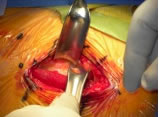

Anterior single incision approach.

Anterior Approach

Dr. Synder’s technique is very similar to that of Professor Kristaps Keggi. at times he uses the Omni-Track table bone hook although the two cases I observed they were not needed.